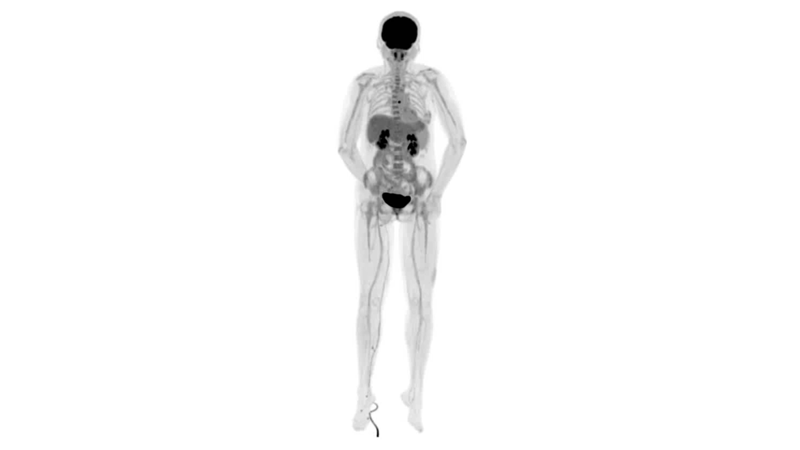

圖例

直腸癌

男,45歲,直腸癌術(shù)后9個(gè)月,發(fā)現(xiàn)肺占位

臨床診斷:直腸區(qū)術(shù)后改變,復(fù)發(fā)伴骶骨受累,雙肺多發(fā)轉(zhuǎn)移